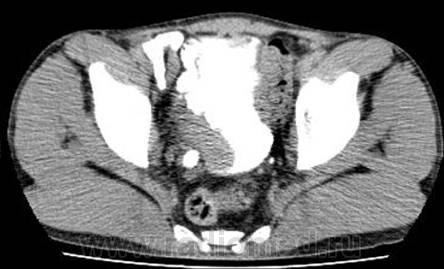

Пол пациента: Мужской пол Тип патологии: Злокачественное новообразование Область исследования: Мочеполовая система Методы исследования: КТ Прадварительно была проведена внутривенная урография. https://radiomed.ru/sites/default/files/styles/case_slider_image/public/user/12/2.predvaritelno.risunok24.jpg?itok=6yKsWOIu https://radiomed.ru/sites/default/files/styles/case_slider_image/public/user/12/3.predvaritelnorisunok25.jpg?itok=fAXoOy_m https://radiomed.ru/sites/default/files/styles/case_slider_image/public/user/12/4predvaritelno.risunok26.jpg?itok=pmVH8o80 ID:10914